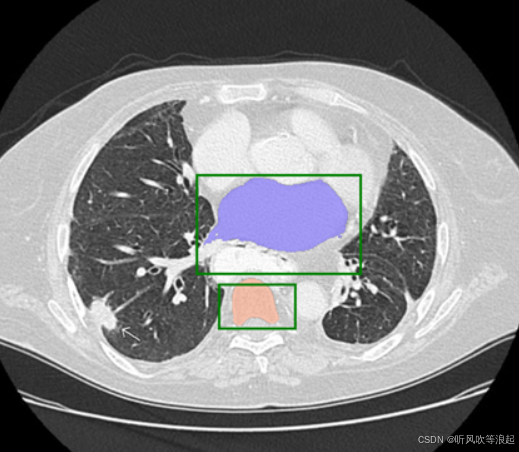

实际测试中,只要用户点在目标区域内,模型基本都能准确分割出对应目标。即使点稍微偏出边界,只要还在目标附近,模型也有一定容错能力。多点几个点,分割结果会更稳定。